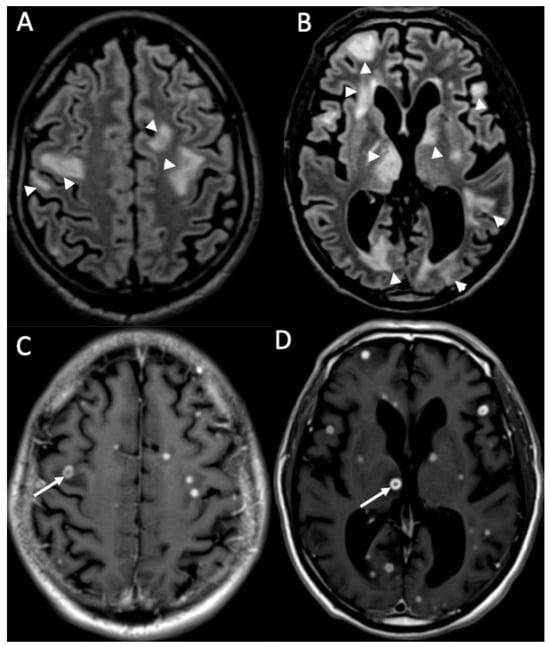

| Cryptococcus Neoformans | • Leptomeningeal enhancement • Cryptococcoma • Gelatinous pseudocysts |

| Candida albicans | • Microabscesses • Vascular lesions |

| Aspergillus fumigatus | • Abscesses • Vascular lesions |